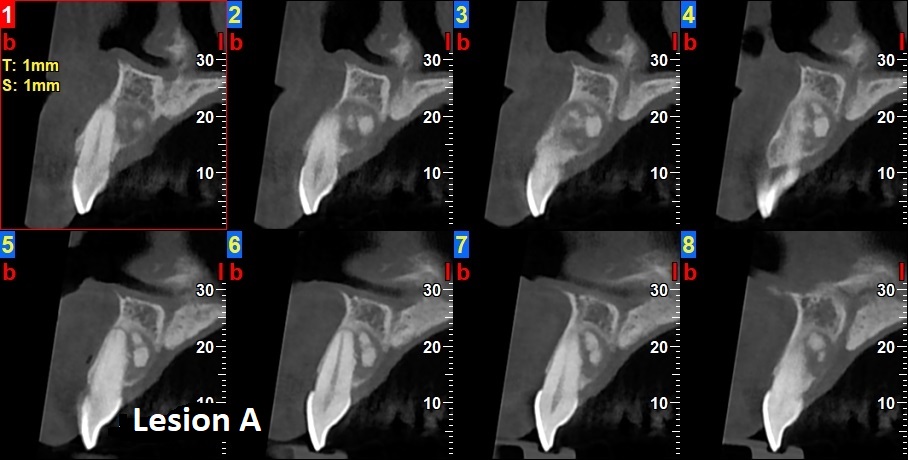

QUIZ 4QUIZ 4Which of the following would you include in your differential diagnosis? (Select one or more correct answers) Which of the following would you include in your differential diagnosis? (Select one or more correct answers)a. Compound Odontomab. Complex Odontomac. Periapical Cemento-Osseous Dysplasia d. Cemento-Ossifying Fibromae. CementoblastomaQUIZ 4Which of the following would you include in your differential diagnosis? (Select one or more correct answers) Which of the following would you include in your differential diagnosis? (Select one or more correct answers)a. Degenerative Arthritisb. Rheumatoid Arthritisc. Osteochondromad. Metastatic Tumore. Aneurysmal Bone CystQUIZ 4Describe your findings from this panoramic radiograph. Describe your findings from this panoramic radiograph.